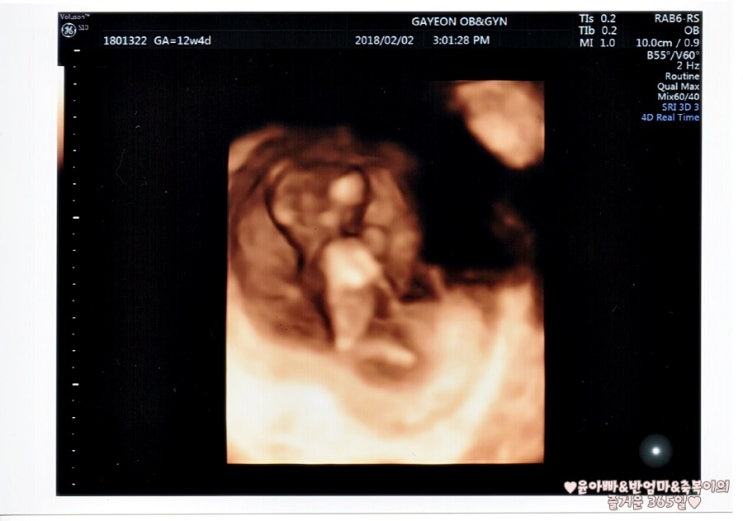

1.1차 정밀초음파&통합선별검사 임신 12주차는 중요한 시기로 아이가 많이 커져 배 초음파가 가능해져 1차 정밀초음파검사와 통합선별검사를 하게 됩니다.

정밀초음파는 1차(10~13주), 2차(20~21주)에 시행되는데, 1차 정밀초음파 검사: 태아목 투명대(NT) 두께 측정으로 태아의 염색체, 심장에 이상이 있는지 확인합니다.보통 2.5mm 미만이 정상입니다(목투명대란 아기를 둘러싼 차양막에서 목까지의 빈 부분입니다.)